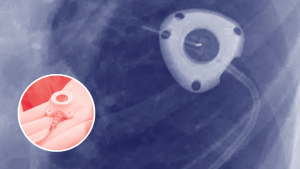

Ethylene Oxide Exposure Litigation: Medical Risks Driving Emerging Mass Tort & MDL Cases

Ethylene oxide (EtO) is a widely used industrial chemical primarily employed for sterilizing medical equipment and manufacturing products such as…